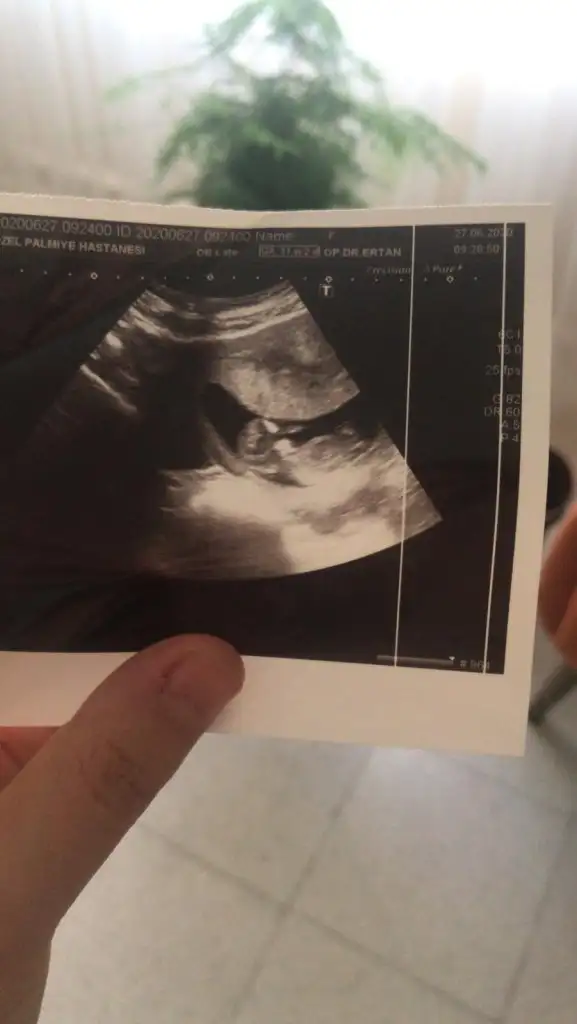

Erkek minnoşunuzKızlar bana da tahminde bulunur musunuz doktor erkeğe benziyor dedi ama benim hala umudum var belki kız olur diyeEki Görüntüle 2656674

Haklısın cuma kontrolü varmış ama cinsiyet belli olur heralde 13+ oldu çünküBuna ne tahmin etsem %50 yarı yarıya tahmin olur çünkü çok erken nu bu haftalarda iki tarafa benzer şimdilik erkek yönünde tutmayabilir yuzde verdim

Erkek gibi sanki